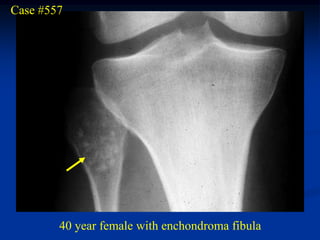

Case #557

40 year female with enchondroma fibula

Bone scan

Sagittal T-1 MRI

Axial T-1 MRI